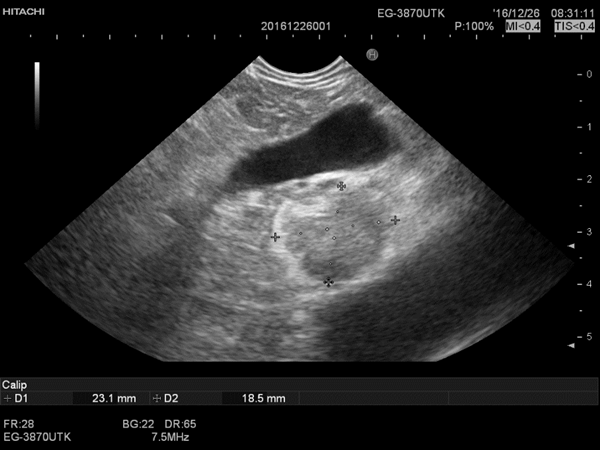

术后恢复良好:血糖保持正常平稳,胰岛素水平恢复正常

消融4日后复查超声内镜后表现为中等偏高回声病灶,血管消失